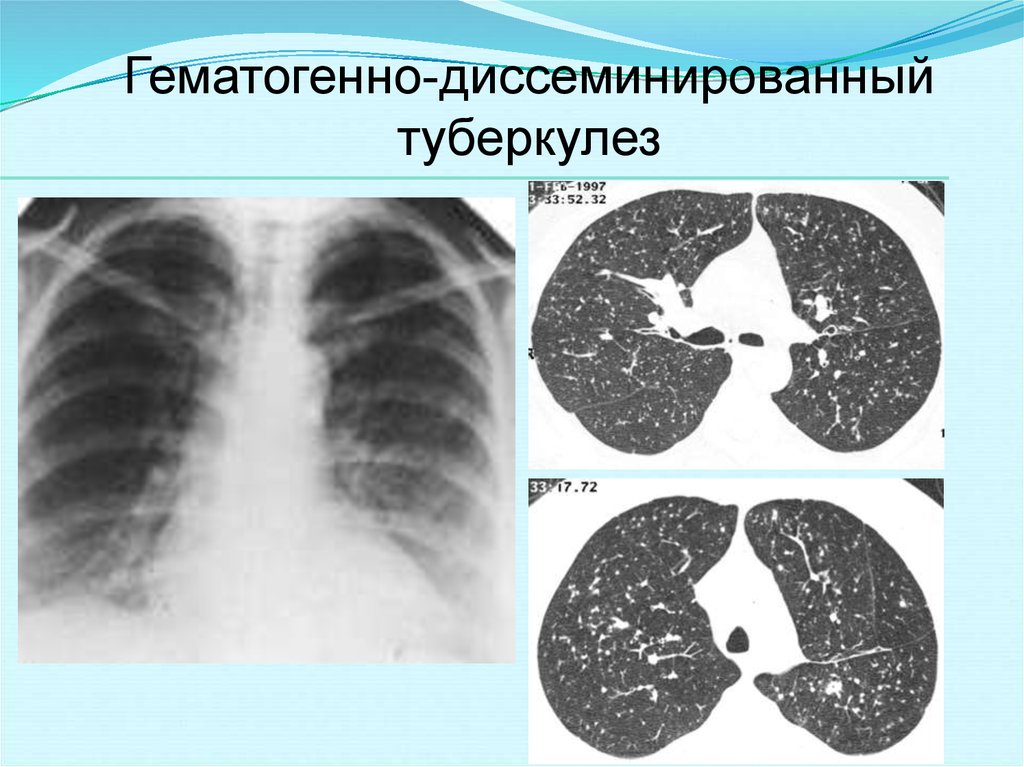

В клинической картине острого гематогенно диссеминированного туберкулеза преобладает